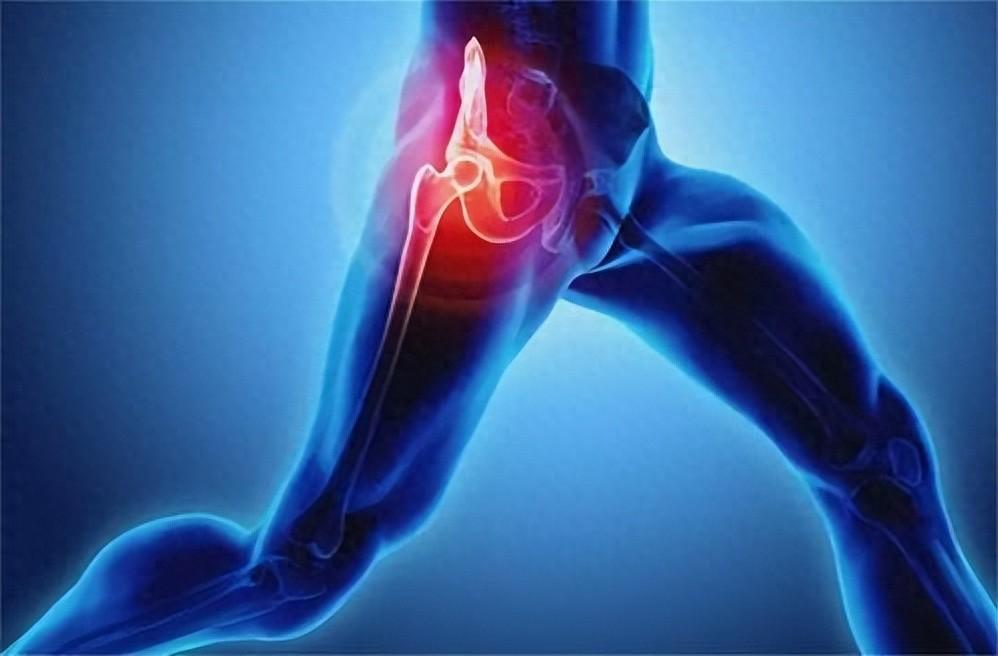

腿抽筋大部分人的肌肉時不時地抽筋,這並無大礙。然而,如果你僅僅在散步時就經常感到大腿、臀部或小腿疼痛或抽筋,就要引起注意了。根據匹茲堡大學醫學中心心髒病專家的說法,這可能是主髂動脈閉塞性疾病的一個跡象。

手臂或肩膀疼痛如果這種疼痛在用力時持續出現,休息時感覺稍好,可能意味著心臟病正在醞釀。然而,如果你突然感到手臂、背部或肩部劇烈疼痛,加上胸部有擠壓感,很有可能是心髒病發作。